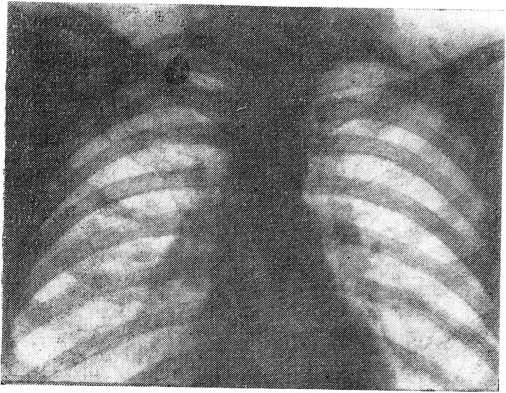

Сопоставляя в таблице 3 стандартные рентгенограммы с флюорограммами различных размеров одного и того же больного, мы идентичность снимков отмечали как «полное совпадение» в диагнозе (рис. 1). Флюорограммы же, не отражавшие в достаточной степени качественной характеристики процесса и затруднявшие качественную диагностику, мы обозначали термином «частичное расхождение» в диагнозе. Расхождение в диагнозе количественного и качественного характера мы отмечали как «несовпадение».

Рис. 1 а

Рис. 1 б

Только по одному случаю при определении диагноза инфильтративного и фиброзно-кавернозного туберкулеза легких на флюорограмме размером 7 X 7 см было отмечено «частичное расхождение» в диагнозе в сравнении с обычной рентгенограммой. В то же время по мелкокадровым флюорограммам при перечисленных формах туберкулеза легких получено: частичных расхождений — 2 при первичном комплексе, 4 — при инфильтративном туберкулезе легких, 4 — при фибрознокавернозном туберкулезе легких.